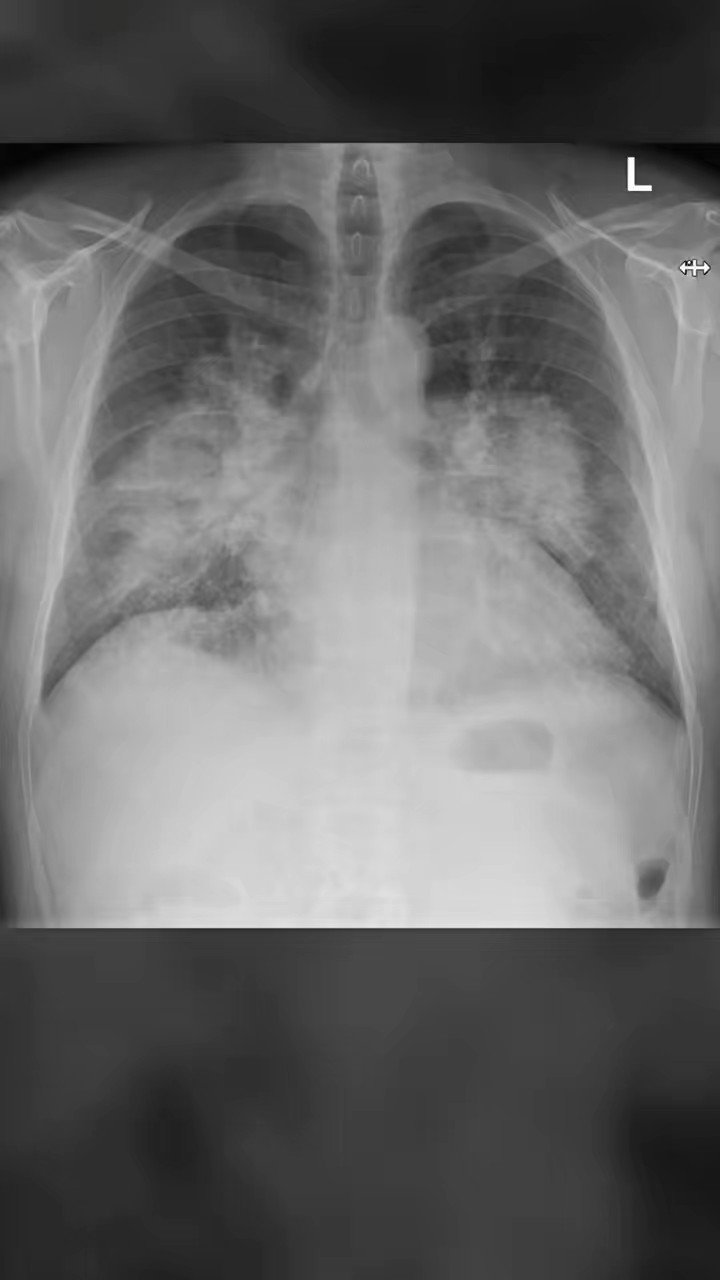

from limmereducation.com

Back to the Basics CHF vs. Chronic Bronchitis Shortness of Breath

What Does A Chest X-Ray Show For Shortness Of Breath Lung inflammation can be acute (rapidly occurring and severe) or chronic (persistent or. It might feel like your chest is tight, you’re gasping for air or you’re working harder to breathe. Dyspnea, or shortness of breath, is the feeling that you can’t get enough air into your lungs. Lung inflammation can be acute (rapidly occurring and severe) or chronic (persistent or. Shortness of breath, medically known as dyspnea, is a sensation of not being able to breathe comfortably or deeply enough. There are no visible nodules, tumors or masses. During a pulmonary function test, you blow into a device called a spirometer, which measures how much. Symptoms may include wheezing, shortness of breath, chest pain, and coughing.